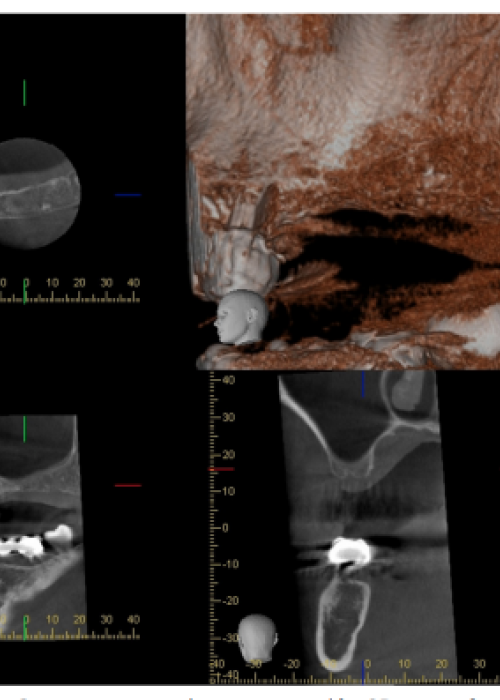

Reubicación quirúrgica de un segundo molar inferior. Presentación de un caso clínico y revisión de la literatura